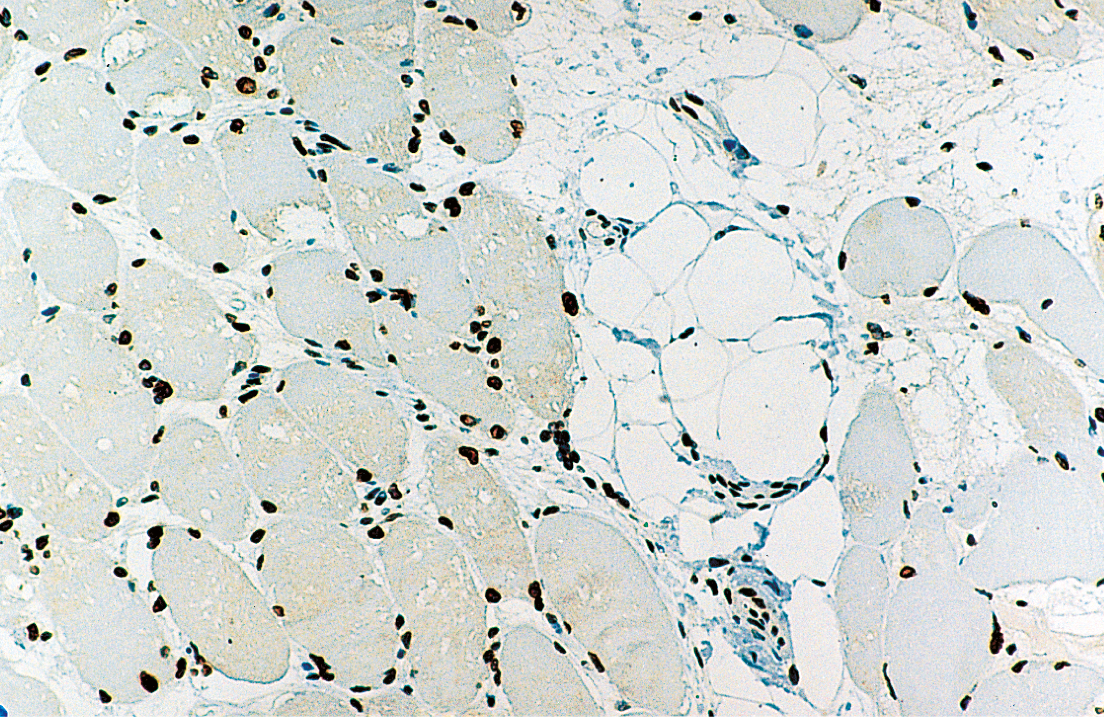

Human skeletal muscle: immunohistochemical staining for Emerin. Note perinuclear staining of all cell nuclei. Emerin: clone 4G5

Emerin befindet sich in der Kernmembran normaler Muskelzellen, und sein Mangel spielt eine wesentliche Rolle bei der Pathologie der EDMD. NCL-EMERIN ist hilfreich zum Nachweis des normalen Genprodukts von STA.